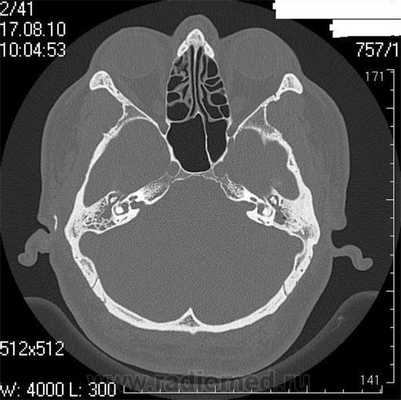

Рис. 1. КТ височных костей пациентки М. а — коронарная проекция: деструктивная полость в пирамиде височной кости, заполненная субстратом неоднородной плотности, капсула лабиринта значительно разрушена на уровне базального и апикального завитков улитки, латерального и верхнего полукружных каналов; б — аксиальная проекция: деструктивная полость с разрушением задней грани пирамиды, передневерхней и нижней поверхности.